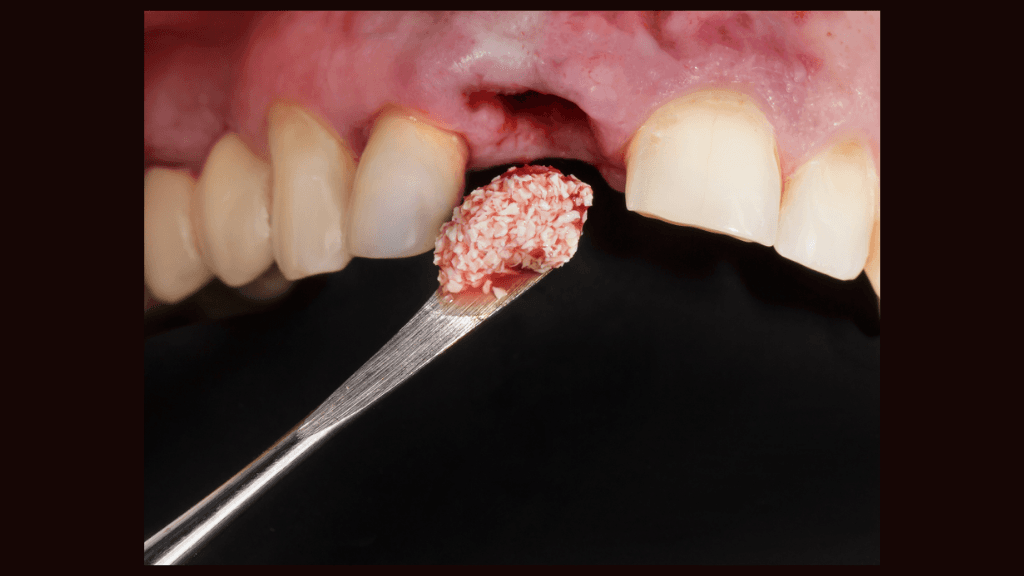

Bone grafting is a surgical procedure that restores or augments bone in the jaw. It is crucial for patients who have experienced bone loss due to periodontal disease or trauma and are seeking dental implants.

We utilize advanced grafting techniques, such as socket preservation and ridge augmentation, to create a sturdy base. This ensures your future dental implants are secure, long-lasting, and aesthetically pleasing.